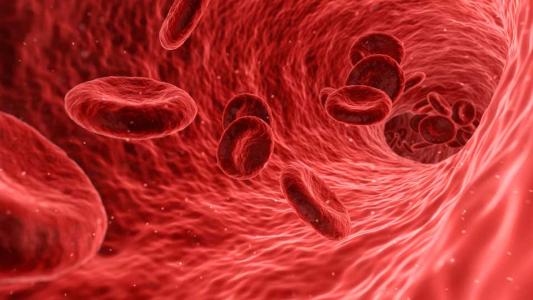

Spraying bacteria onto the skin can treat eczema

The bacteria in your microbiome ward off infections and help keep your skin healthy.